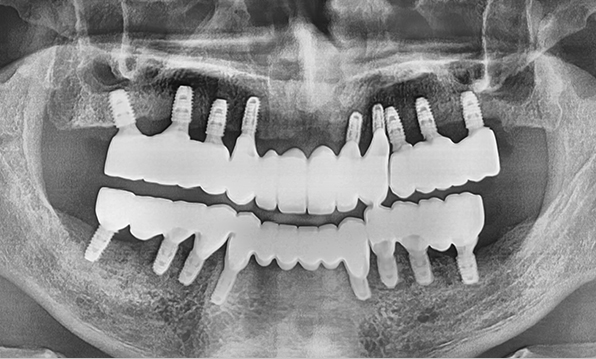

Case 02

Before After